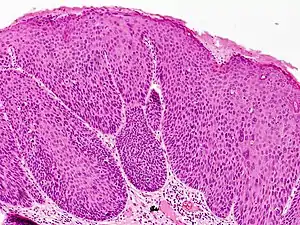

Bowenoid papulosis

Bowenoid papulosis is a cutaneous condition characterized by the presence of pigmented verrucous papules on the body of the penis.[1]: 730 [2]: 408 They are associated with human papillomavirus, the causative agent of genital warts.[3] The lesions have a typical dysplastic histology and are generally considered benign, although a small percentage will develop malignant characteristics.

It is considered as a pre-malignant condition. Other terms used to describe the condition are: Erythroplasia of Queyrat, Squamous cell carcinoma in situ and Bowen's disease. The term bowenoid papulosis was coined in 1977 by Kopf and Bart and is named after dermatologist John Templeton Bowen.[4][5][6] The term "intraepithelial neoplasia" defines a premalignant intraepithelial change.